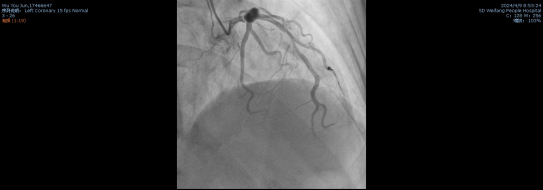

患者的一系列结果与症状都指向急性心肌梗死,立即在北辰院区行冠状动脉造影术,冠脉造影结果: